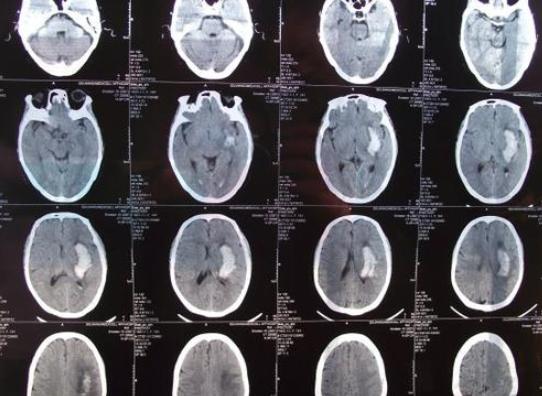

「脳卒中」は中国医学の概念で、中臓と中経に分けられ、中臓は現代医学でいう脳出血に相当し、中経は急性脳梗塞に相当する。脳出血も脳梗塞も非常に重篤な脳血管疾患であり、脳出血の死亡率と後遺障害率は非常に高いが、脳梗塞の死亡率は脳出血より低いが、後遺障害率も非常に高く、脳出血と脳梗塞の患者の大部分は四肢片麻痺、言語障害、嚥下障害などの後遺症を残す。

これらの後遺症が回復するかどうかは、まず出血量や脳梗塞の大きさや部位と密接な関係がある。例えば、一度に数十ミリリットルというような大量の脳出血が、手足の運動をつかさどる脳組織の部位に起こった場合、出血の圧迫により、この部位の脳神経は非常に早く損傷を受け、神経の損傷は不可逆的であるため、症状はすぐに現れ、回復することは容易ではありません。もう一つの例は大規模な脳梗塞で、これも同じ理由で、脳神経の損傷による急性の虚血で、この時、もし適時に血栓溶解で血管を再び痛めさせれば、脳組織の損傷はさらに悪化せず、比較的軽い程度にとどまり、手足の症状も軽く、その後、運動の回復を通じて、正常に近いレベルまで回復することができる。

次に治療と回復の場合である。前述の脳梗塞の適時血栓溶解療法のように、治療が適時であればあるほど、回復の程度は高くなる。しかし、これは絶対的なものではなく、多くの脳血管疾患患者は、発症が重篤であれば、すぐに病院で治療を受けても後遺症が残る可能性があり、脳梗塞の血栓溶解療法のように、すべての人にとって必ずしも良い結果が得られるとは限りません。

適時のリハビリ運動は非常に重要である。一般的に言って、急性脳血管障害が回復期に入る限り、機能回復訓練を考慮すべきであり、このようなリハビリ運動は早ければ早いほど、後の回復が良好になる可能性があるが、完全に元通りになるわけではない。一般的に言って、脳血管疾患の回復期は発症後半年以内、特に最初の3ヶ月以内が機能回復にとって最も重要な時期である。半年以上経過しても効果がある場合もあるが、早期回復の効果ほど明らかでないことは確かである。

全体として、脳血管障害の発症が軽く、適時の治療とリハビリテーションを受けた人は、後期の回復がよく、ほとんど正常なレベルまで回復する人はごく少数である。一方、発症があまりに重く、適時の治療や早期のリハビリ訓練を受けなかった人は、予後が悪くなる傾向があり、そのほとんどが生涯にわたって後遺症を残すことになる。